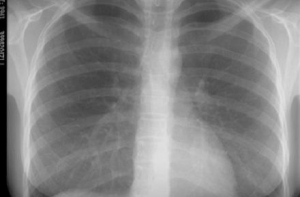

Работать кабинет будет с 8.00 до 20.00 (24—29 марта), и с 13.00 до 20.00 (23 марта) Жители столицы смогут бесплатно пройти флюорографию, которая в клиниках обходится в 40 грн. (если без направления терапевта). У входа на Южный вокзал, что на улице Ползунова, в честь дня борьбы с туберкулезом фонд Рината Ахметова «Развитие Украины» открыл мобильный рентген-кабинет. Зайти в него с 23 по 29 марта сможет любой желающий и бесплатно сделать цифровую флюорографию, получить на руки снимок и заключение рентгенолога. Работать кабинет будет с 8.00 до 20.00 (24—29 марта), и с 13.00 до 20.00 (23 марта). Кроме того, столичная мэрия зовет киевлян проверяться на ВИЧ. Для этого в городе работают пять «кабинетов доверия», где пройти тест и сделать анализы на заболевание можно анонимно и бесплатно. Посетить их можно на ул. Трехсвятительской, 7, Отдыха, 11, бул. Высоцкого, 8, Бориспольской, 30-а и на 40-летия Октября, 59-а. |